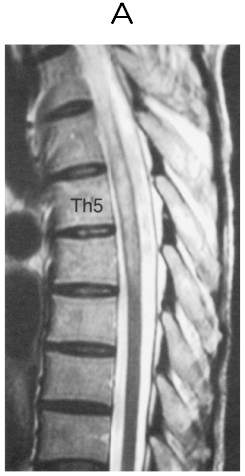

48歳の女性。両下肢筋力低下を主訴に来院した。1年前に右眼視力低下があり,眼科で加療されて症状は改善した。3日前から両下肢の脱力感としびれ感を自覚していた。これらの症状が徐々に悪化し,本日起床時に起き上がるのが困難となったため,夫が救急車を要請し入院した。意識は清明。血圧112/64mmHg。脈拍80/分,整。胸腹部に異常を認めない。神経診察では脳神経領域に異常を認めない。上肢には麻痺はなく,腱反射は正常である。下肢筋力は両側の近位筋,遠位筋ともに徒手筋力テストで2程度に低下している。下肢腱反射は亢進し,Babinski徴候は両側陽性である。胸骨下縁から下で温痛覚の低下がみられる。血液所見,血液生化学所見に異常を認めない。脳脊髄液所見は細胞数69(多核球60,単核球9)/mm3(基準0~2),蛋白62mg/dL(基準15~45),糖62mg/dL。胸椎MRIのT2強調矢状断像(A)と病変部の水平断像(B)を下に示す。